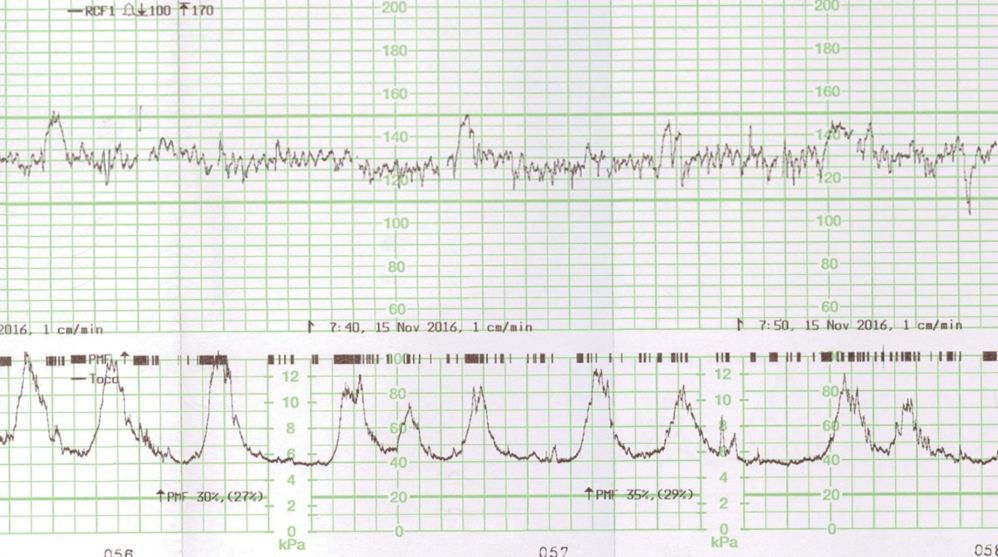

Voici le résultat de la cardiotocométrie et de l’échographie du col réalisée par voie endovaginale.

Figure 4 (Rodolphe Matias de Sousa, La Revue du Praticien)

Une menace d’accouchement prématuré se définit comme des contractions utérines régulières et douloureuses (ici 5 par dix minutes visibles à la tocométrie) et un col raccourci ou modifié cliniquement (ici mesuré à 20 mm à l’échographie endovaginale). Un col non modifié est dit long, tonique, postérieur, fermé avec une présentation fœtale non sollicitante.